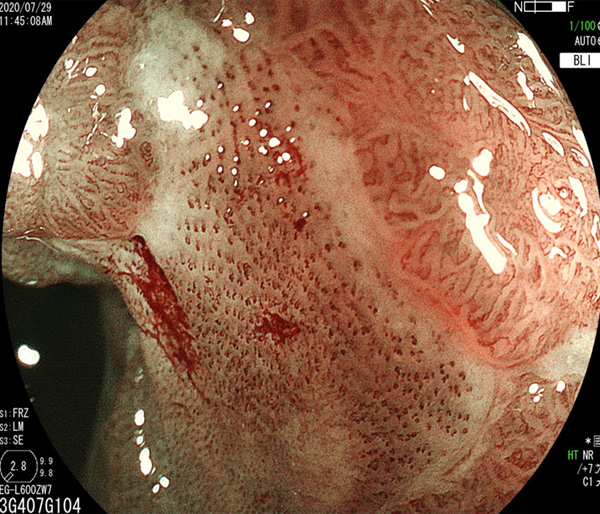

2026年1月24日開催の第19回研究会でご提示した検討症例です。 (画像をクリックすると拡大します)

2025年7月19日開催の第18回研究会でご提示した検討症例です。 (画像をクリックすると拡大します)

2025年1月11日開催の第17回研究会でご提示した検討症例です。 (画像をクリックすると拡大します)

2024年6月29日開催の第16回研究会でご提示した検討症例です。 (画像をクリックすると拡大します)

2024年1月6日開催の第15回研究会でご提示した検討症例です。 (画像をクリックすると拡大します)

2023年7月1日開催の第14回研究会でご提示した検討症例です。 (画像をクリックすると拡大します)

2023年1月21日開催の第13回研究会でご提示した検討症例です。 (画像をクリックすると拡大します)

2022年7月2日開催の第12回研究会でご提示した検討症例です。 (画像をクリックすると拡大します)

2022年1月22日開催の第11回研究会でご提示した検討症例です。 (画像をクリックすると拡大します)

2021年6月26日開催の第10回研究会でご提示した検討症例です。 (画像をクリックすると拡大します)

2021年1月23日開催の第9回研究会でご提示した検討症例です。 (画像をクリックすると拡大します)

2020年1月25日開催の第8回研究会でご提示した検討症例です。 (画像をクリックすると拡大します)

2019年1月12日開催の第6回研究会でご提示した検討症例です。 (画像をクリックすると拡大します)

2018年6月30日開催の第5回研究会でご提示した検討症例です。 (画像をクリックすると拡大します)

2017年7月15日開催の第3回研究会でご提示した検討症例です。 (画像をクリックすると拡大します)

2017年1月7日開催の第2回研究会でご提示した検討症例です。 (画像をクリックすると拡大します)

2016年6月4日開催の第1回研究会でご提示した検討症例です。 (画像をクリックすると拡大します)